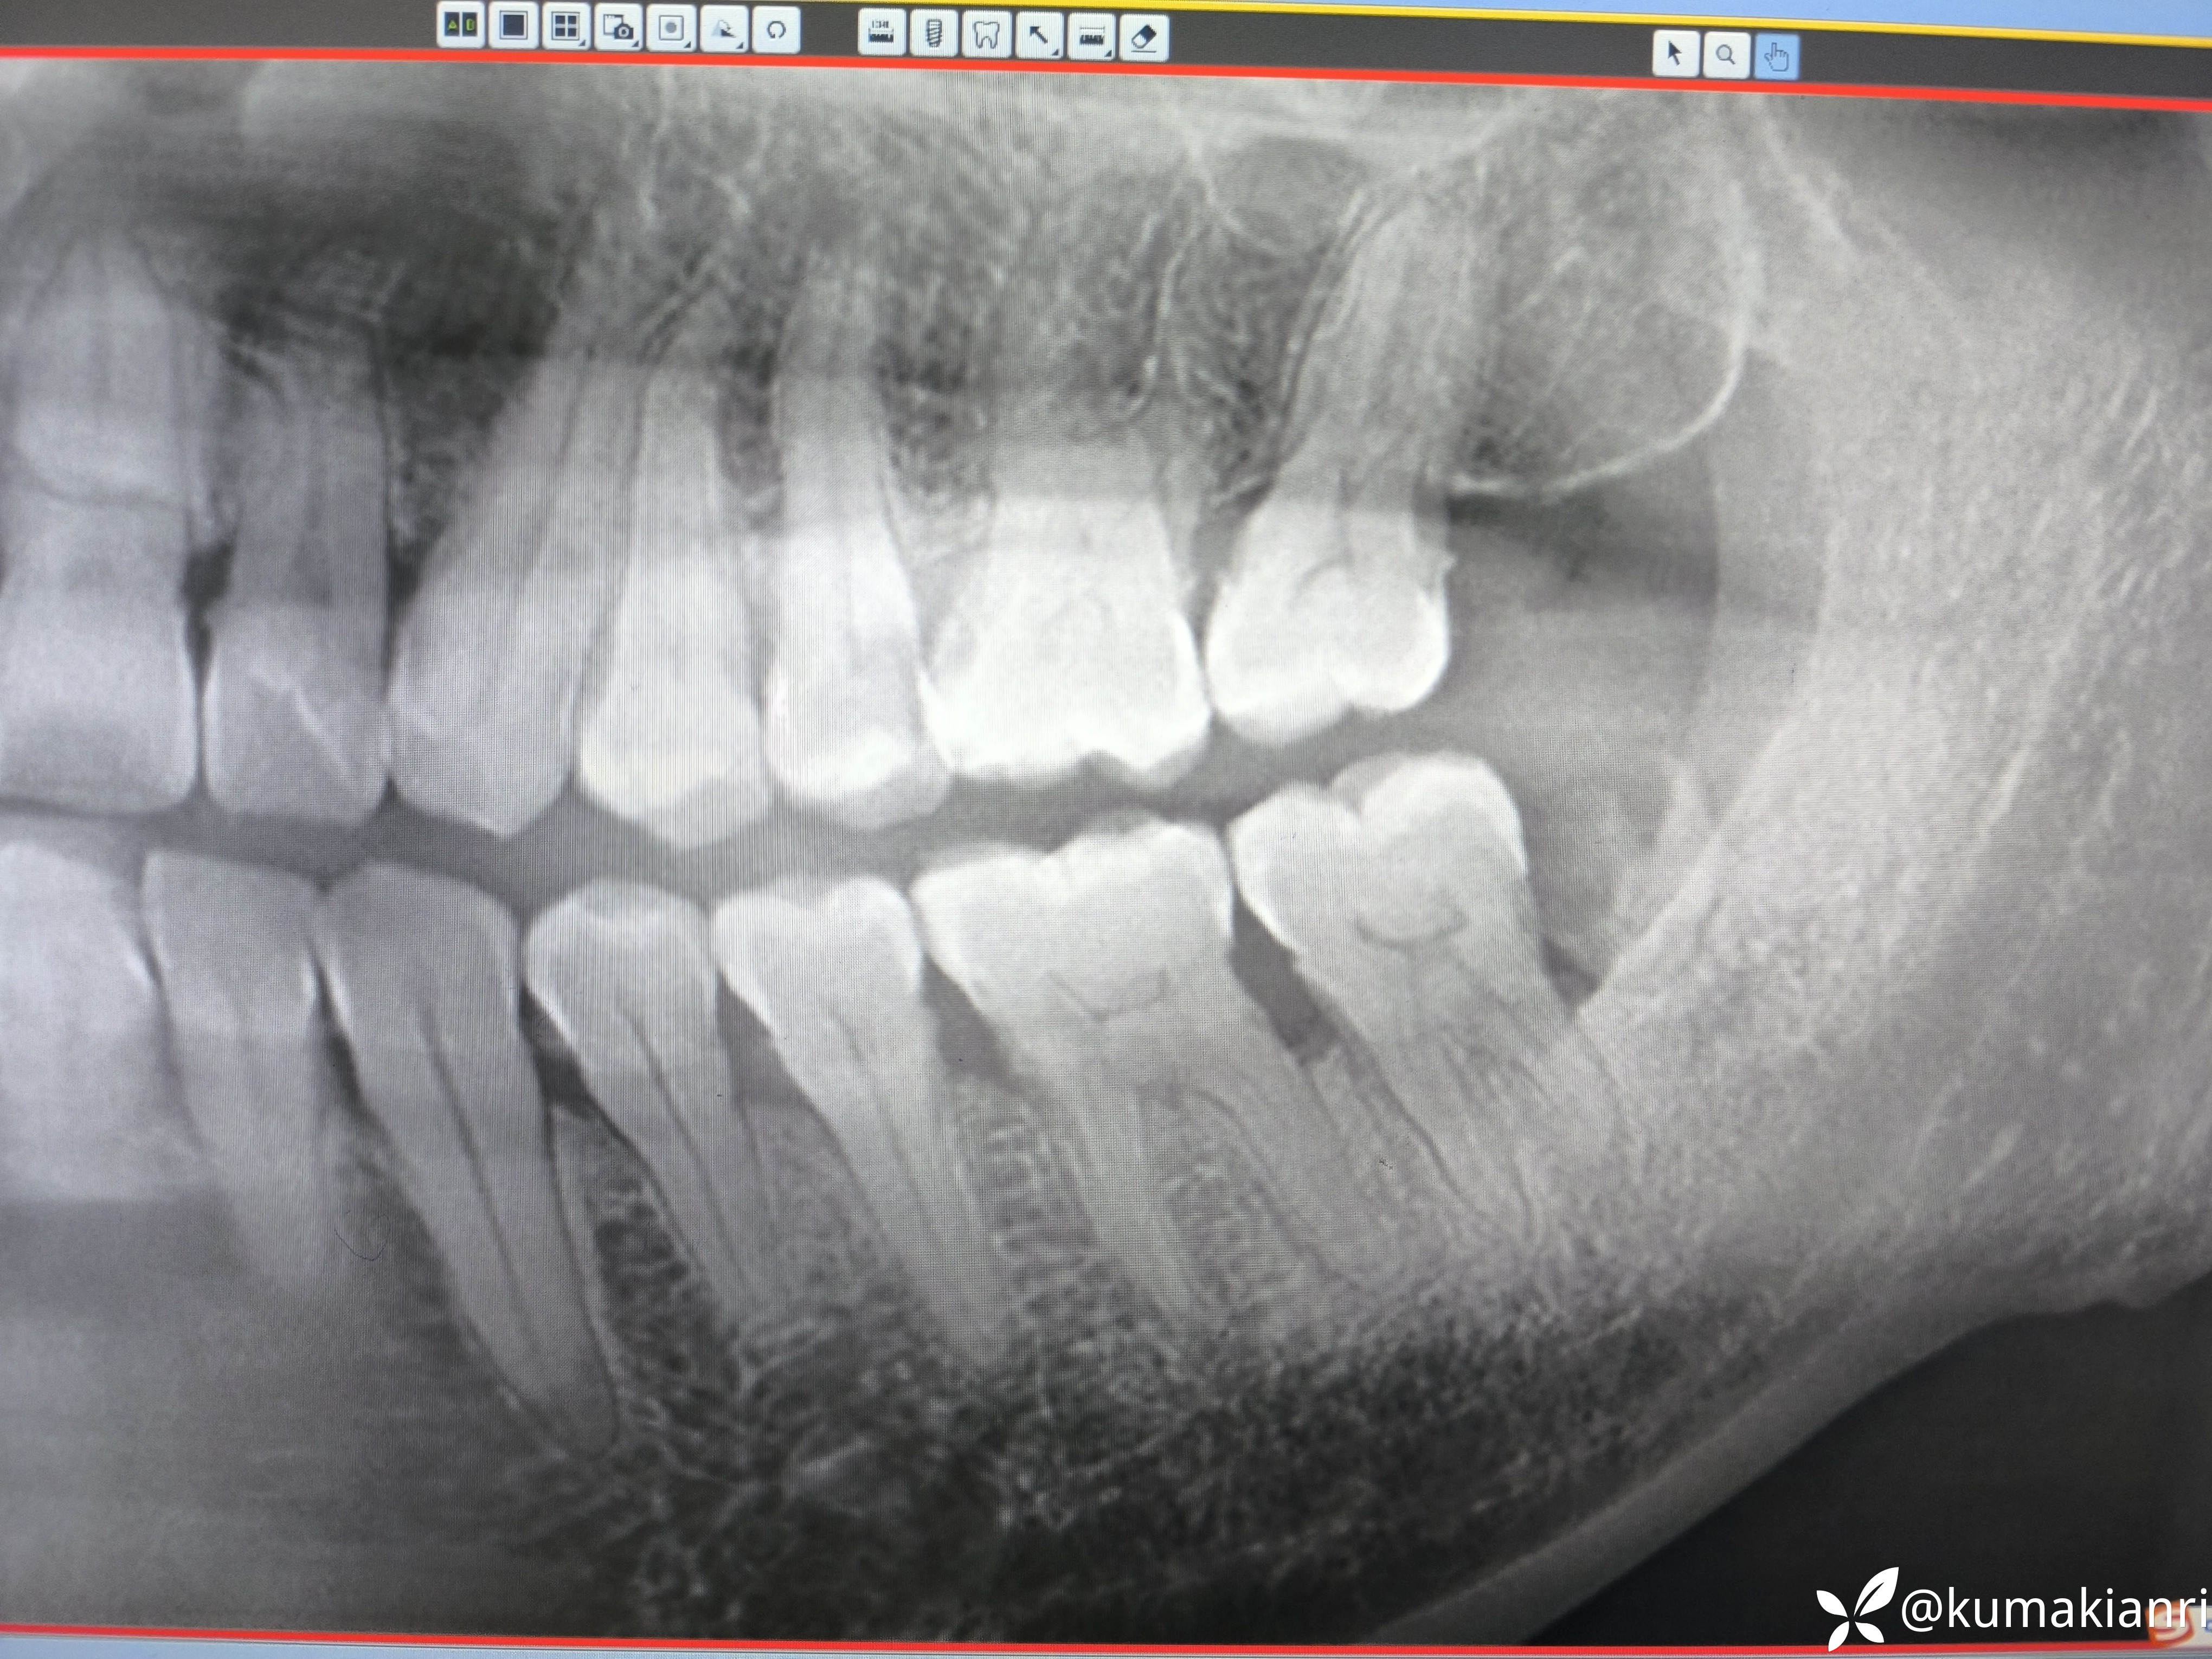

检查:37叩诊+,冷+,牙龈萎缩3-4mm,根颈1/3暴露,远中邻面龋坏;38牙冠大面积龋坏